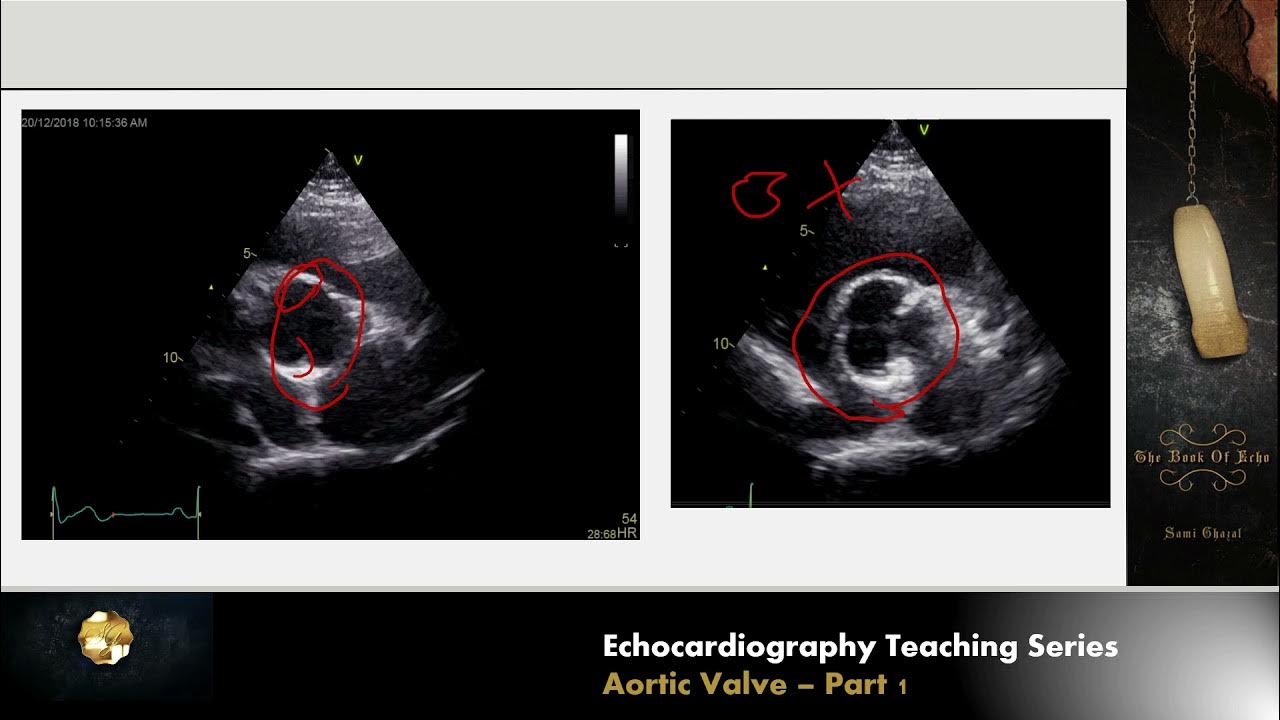

From www.youtube.com

Lecture 9 Aortic Valve Part 1 YouTube Motion Artifact At The Aortic Root Advances in ct technology have allowed motionless imaging of the chest and. Ct can image the entire aorta and its branches with high spatial resolution and fast acquisition. Advances in ct technology have allowed motionless imaging of the chest and abdomen, leading to an increased visualization. Motion Artifact At The Aortic Root.